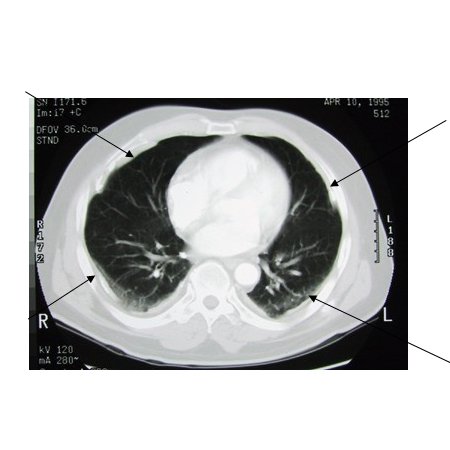

Asbestosis

CT scan of the chest showing multiple examples of pleural thickening most with calcification (arrows)

From the personal collection of Kenneth D. Rosenman MD